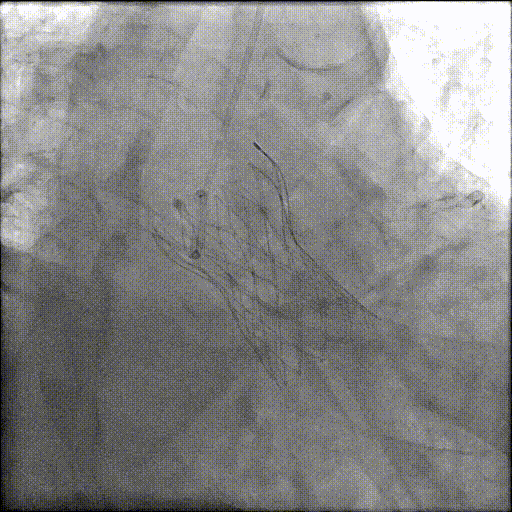

手术团队建立好通路后,沿着导丝将一个未充气的球囊送至主动脉瓣位置。球囊迅速充气膨胀,将严重钙化、几乎无法打开的「旧门」强行撑开。球囊预扩张后,真正的「主角」——压缩在输送系统中的生物瓣膜登场。团队将输送系统沿导丝送至主动脉瓣区域,在 DSA 透视和超声的双重引导下,精确调整瓣膜位置,确保新瓣膜既不会堵塞冠状动脉开口,也不会影响二尖瓣功能。当瓣膜位置确认无误后,开始缓慢释放瓣膜。

由于患者基础心功能极差,不能耐受瓣膜的多次回收释放。团队凭借丰富经验,在默契配合下仅一次就迅速将瓣膜完美植入既定位置。瓣膜释放后,跨瓣压瞬间清零。通过超声和主动脉根部造影评估手术效果:瓣膜释放位置正常,瓣膜启闭正常,无瓣周漏,术后转入 ICU 密切监测。

胡爷爷的 PCI+TAVR 一站式手术顺利完成。术后心衰症状得到明显缓解,心率血压趋于平稳;6 小时后,可以在床上简单活动;术后第二天就转回普通病房,他已经能够下床站立。复查心脏彩超显示,他的左心室舒张末径较术前有所减小,射血分数从术前的 42% 上升至 48%,心脏整体情况得到明显改善。